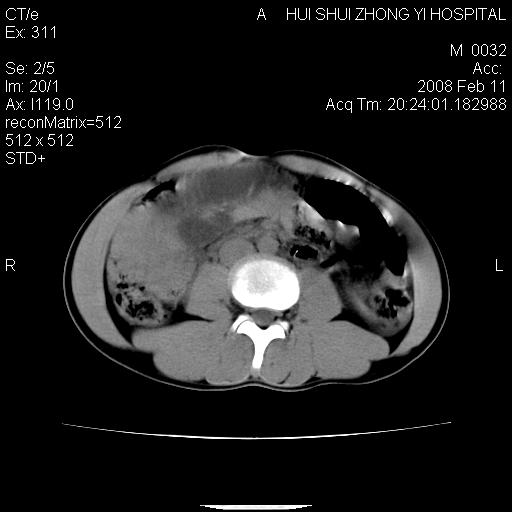

8年前曾在贵洲省人民医院b超诊断为肝内胆管结石。现腹痛剧烈,现发烧、头痛、恶心呕吐县医院b超示胆囊肿大大小159*46mm,囊内见6*5mm强回声光团,胆各总管内径56mm。提示:胆囊结石、急性胆囊炎、胆总管重度扩张。

胆囊结石.急性胆囊炎.重度胆管扩张.右侧胸腔少量积液,建议ct增强

考虑先天性胆管囊肿;胆囊增大并结石。右侧胸腔少量积液,建议ct增强。

caroli囊肿并囊内结石。胆囊增大并胆结石。典型!

先天性胆管囊肿,胆囊结石、胆囊增大,右侧少量胸腔积液。